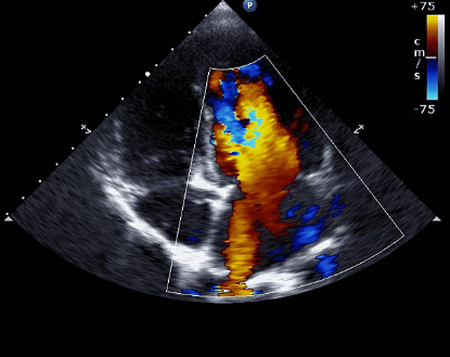

Вторичные функциональные нарушения при дилатационной кардиомиопатии на эхокардиографии включают расширение митрального кольца и неполное закрытие створок митрального клапана, ответственных за связанной с этим функциональной митральной регургитацией. Доказательства в пользу малого сердечного выброса говорит снижение экскурсии митрального клапана, расширенные предсердные полости, расширение ПЖ и иногда наличие верхушечного пристеночного тромба. Задержка межжелудочковой проводимости (блокада левой или правой ножки пучка Гиса) - это распространенные явления и способствует дальнейшему развитие сердечной дисфункции, вызывая внутрижелудочковую механическую диссинхронию. Рекомендуется ближайших родственников пациентов с дилатационной кардиомиопатией пройти эхокардиографический скрининг из-за высокой заболеваемости (20%-50%) семейных дилатационных кардиомиопатий. Четкие клинические признаки этого семейного заболевания не выявлены. В некоторых случаях дилатационных кардиомиопатий на эхокардиографии размер и функция ЛЖ нормализуется при правильном лечении (обратное ремоделирование).

Митральная регургитация является частой при дилатационной кардиомиопатии и связано с процессом ремоделирования ЛЖ. Постепенно створки митрального клапана становяться более растянутыми из-за смещения верхушечных сосочковых мышц и региональной перестройки и митральная регургитация становится хуже. Митральный клапан площадью 6 см2, или более обычно ассоциируется с тяжелой митральной регургитацией. Лечение направлено на обратное ремоделирование и уменьшает митральную регургитацию, а также улучшает систолическую функции ЛЖ. Состояние давления в легочной артерии оценивается от скорости трикуспидальной регургитации является также прогностическим критерием при дилатационной кардиомиопатии. Пациенты со скоростью трикуспидальной регургитации более 3 м/с имеют более высокий уровень смертности, более высокую частоту сердечной недостаточности, и более значительно частые госпитализации, чем пациенты, с более низкой скоростью трикуспидальной регургитации. Высокие скорости трикуспидальной регургитации наблюдаются обычно у больных, которые имеют картину ограничительного характера диастолического наполнения. Таким образом, ограничительный паттерн диастолического наполнения ЛЖ и высокая скорость трикуспидальной регургитации определяют пациентов которые имеют увеличенный риск высокой смерти и сердечной недостаточности.